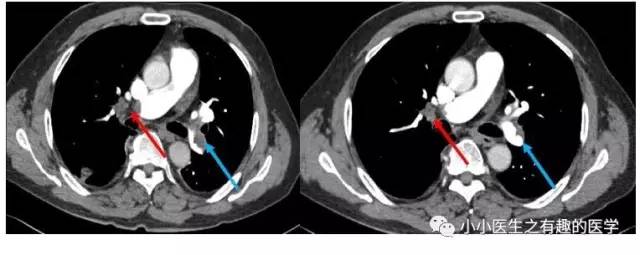

血栓太小了?来几个大的给你看看。首先,看看大扯蛋血栓。医学上,有种血栓叫骑跨血栓,很危险,骑跨:听着很拗口,也不形象,叫扯蛋血栓更形象。

部分学者认为骑跨血栓风险高,即使血流动力学稳定(无休克、血压下降等)也应该给予强有力的治疗:外科手术取栓、介入取栓、溶栓治疗,迅速溶解血栓恢复肺循环血流。真是扯着蛋了。

广州呼研所报道的一例:扯蛋血栓。

入院后给予伊诺肝素钠皮下注射,第2天患者气促较前加重。体检:呼吸27次/分,Sp02:90%(吸氧4 L/min),血压103/62 mmHg。家属签署同意书后,给予重组人组织纤维蛋白溶酶原激活物50mg,静脉滴注2 小时,溶栓后患者气促缓解。

治疗后复查,血栓基本溶解。